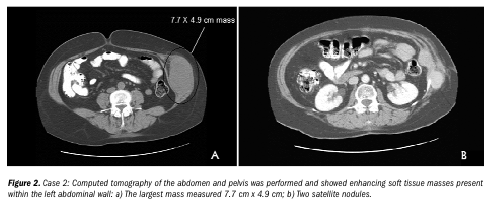

Case 2. Ms. S, a 54-year-old woman, was seen in the surgical clinic with a left abdominal wall mass. She had been treated abroad for a presumed soft tissue sarcoma approximately 9 months earlier. At that time, she underwent excisional biopsy and a subsequent course of external beam radiation. Results of an ultrasound-guided biopsy performed at one of the authors’ institutions demonstrated spindle cell neoplasm. Computed tomography of her abdomen and pelvis showed enhancing soft tissue masses present within the left abdominal wall – the largest mass measured 7.7 cm x 4.9 cm with two satellite nodules (see Figure 2a,b).